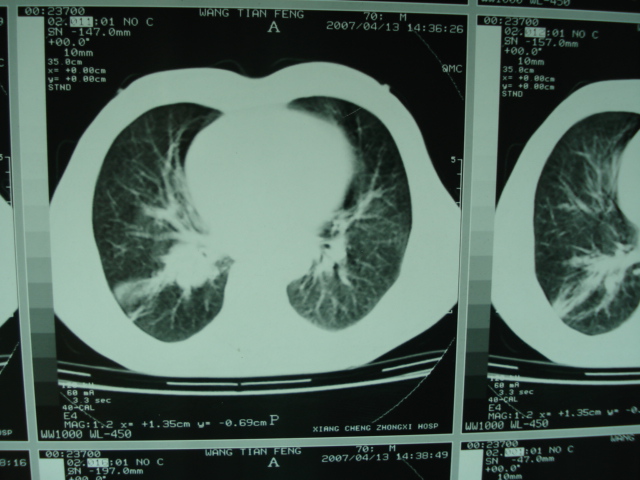

以下是引用狙击手在2007-4-18 20:17:00的发言:[br]原:2007/1/22号ct片:右肺上叶可见片状、云雾状高密度影,右肺上叶后段可见三角形高密度影,尖端指向肺门,右肺上叶后段支气管壁不规则增厚,管腔不规则增厚,纵隔未见肿大淋巴结.[br] 今ct:右肺上叶片状影增大,右肺上叶后段不张及右肺上叶后段支气管壁不规则增厚未见变化,右肺下叶背段支气管壁不规则增厚.[br] 如果考虑肺结核,但从临床证据看竟然没有一项支持肺结核,不知患者是否已经过正规抗结核治疗。没有的话,3个月了前后片看起来变化不大,似乎有不太符合肿瘤征象,不知患者是否抗炎治疗过,下叶支气管增粗还是要高度警惕,同意楼主意见,将常规病理,生化检查再做一遍。[br]

以下是引用狙击手在2007-4-18 20:17:00的发言:[br]原:2007/1/22号ct片:右肺上叶可见片状、云雾状高密度影,右肺上叶后段可见三角形高密度影,尖端指向肺门,右肺上叶后段支气管壁不规则增厚,管腔不规则增厚,纵隔未见肿大淋巴结.[br] 今ct:右肺上叶片状影增大,右肺上叶后段不张及右肺上叶后段支气管壁不规则增厚未见变化,右肺下叶背段支气管壁不规则增厚.[br] 如果考虑肺结核,但从临床证据看竟然没有一项支持肺结核,不知患者是否已经过正规抗结核治疗。没有的话,3个月了前后片看起来变化不大,似乎有不太符合肿瘤征象,不知患者是否抗炎治疗过,下叶支气管增粗还是要高度警惕,同意楼主意见,将常规病理,生化检查在做一遍。[br]